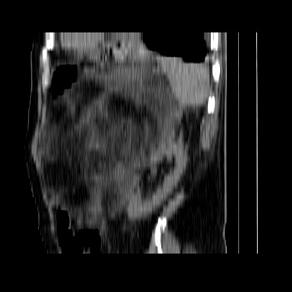

标题: CT21671:男,88岁,左上腹包块 [打印本页]

标题: CT21671:男,88岁,左上腹包块

患者因咳嗽而住院,自觉右上腹包块,无其他不适。

左侧腹膜后脂肪肉瘤。